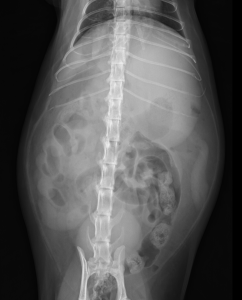

今回治療させていただいた猫ちゃんは、数日前から頻回嘔吐しており、ぐったりしているとの主訴で来院されました。レントゲン検査では、腸が手繰られた所見があり、お腹に漏れたガスも確認されました。